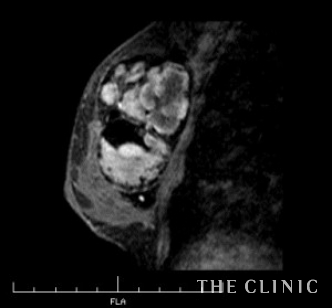

エコーではカプセルが厚く、内部が描出されないためMRI検査を行いました。

MRI画像です。

左はバッグの内部に高信号領域を認めました。

摘出したバッグです。左はカプセル内に血腫を認めました。